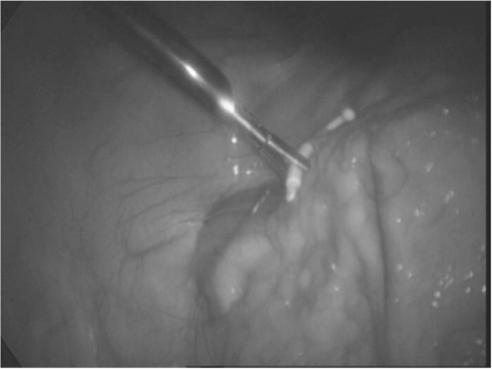

Levonorgestrel-containing intrauterine contraceptive devices, marketed as Mirena (Bayer HealthCare Pharmaceuticals, Inc. Australia) are widely used in contemporary gynecology, primarily as an effective method for contraception and for control of menstrual disorders like menorrhagia and dysmenorrhea. In this article, the authors report 2 cases of Mirena migration following intrauterine insertion by general practitioners (family physicians). In the first case, the contraceptive device had moved to the patient's right iliac fossa just anterior to the cecum and, in the second, within the peritoneal cavity close to the left leaf of the diaphragm. Both patients underwent uneventful laparoscopic retrieval of the devices.

含左炔诺孕酮的宫内节育器,商品名为曼月乐(拜耳医疗保健制药公司澳大利亚分公司),在当代妇科中广泛使用,主要作为一种有效的避孕方法,用于控制月经过多和痛经等月经紊乱。在本文中,作者报告了2例由全科医生(家庭医生)宫内放置曼月乐后发生移位的病例。第一例中,避孕装置移至患者右髂窝,恰好在盲肠前方;第二例中,移至腹膜腔内靠近膈肌左叶处。两名患者均通过腹腔镜顺利取出了节育器。